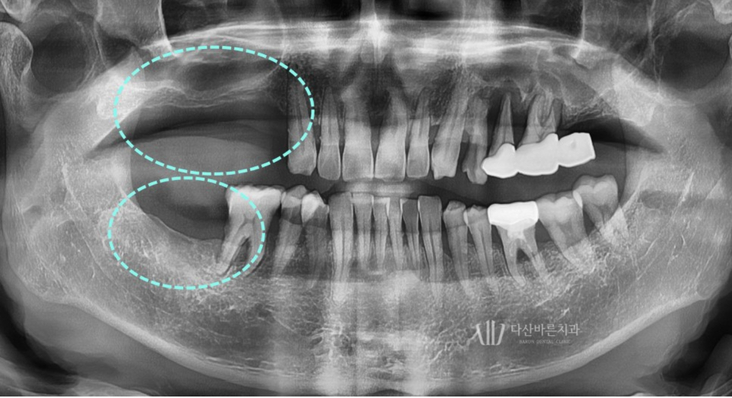

Bệnh nhân này đến bệnh viện với tình trạng

mất răng hàm trên và răng phải đã lâu.

Thoạt nhìn, bệnh nhân đã mất quá nhiều xương nướu để có thể

cấy ghép implant nhưng đã chụp CT 3D để chẩn đoán chính xác hơn độ dày và mật độ xương.

Vì răng đã mất lâu ngày và xương hàm bị mất nhiều

nên cần phải trồng răng implant ghép xương.

Sau khi ghép xương, vị trí và góc đặt implant được lên kế hoạch thông qua quy trình mô phỏng.